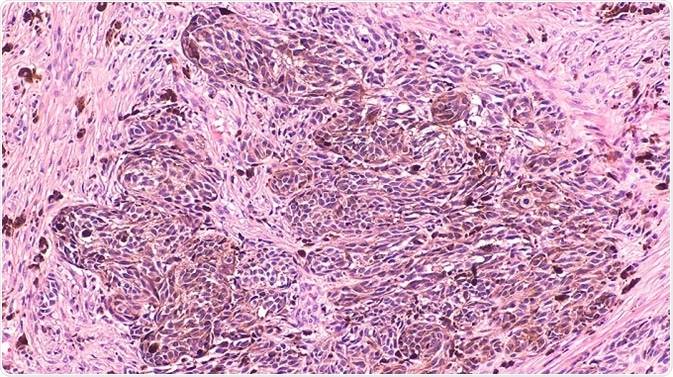

© David Litman/Shutterstock.com

Melanoma is a destructive form of skin cancer and treating advanced-stage melanomas is difficult due to the fact that tumors develop resistance to most of the therapies at this stage, including drugs targeting oncogenic BRAFV600E. Moreover, strong responses to immune checkpoint therapies are observed in only one-third of melanoma patients.

Apart from targeting tumor cells, it has been proposed that targeting infiltrating fibroblasts present in the tumor microenvironment (TME) is a novel approach to treat melanoma. Earlier studies propose that an active interaction between fibroblasts and melanoma cells promotes tumor growth and therapy resistance.

In addition to fibroblasts, immune cells such as B cells, T cells, macrophages, and neutrophils are also present in the tumor stroma. Cross-talk between malignant and immune cells happens either directly through cell–cell interactions or by soluble mediators such as cytokines and growth factors.